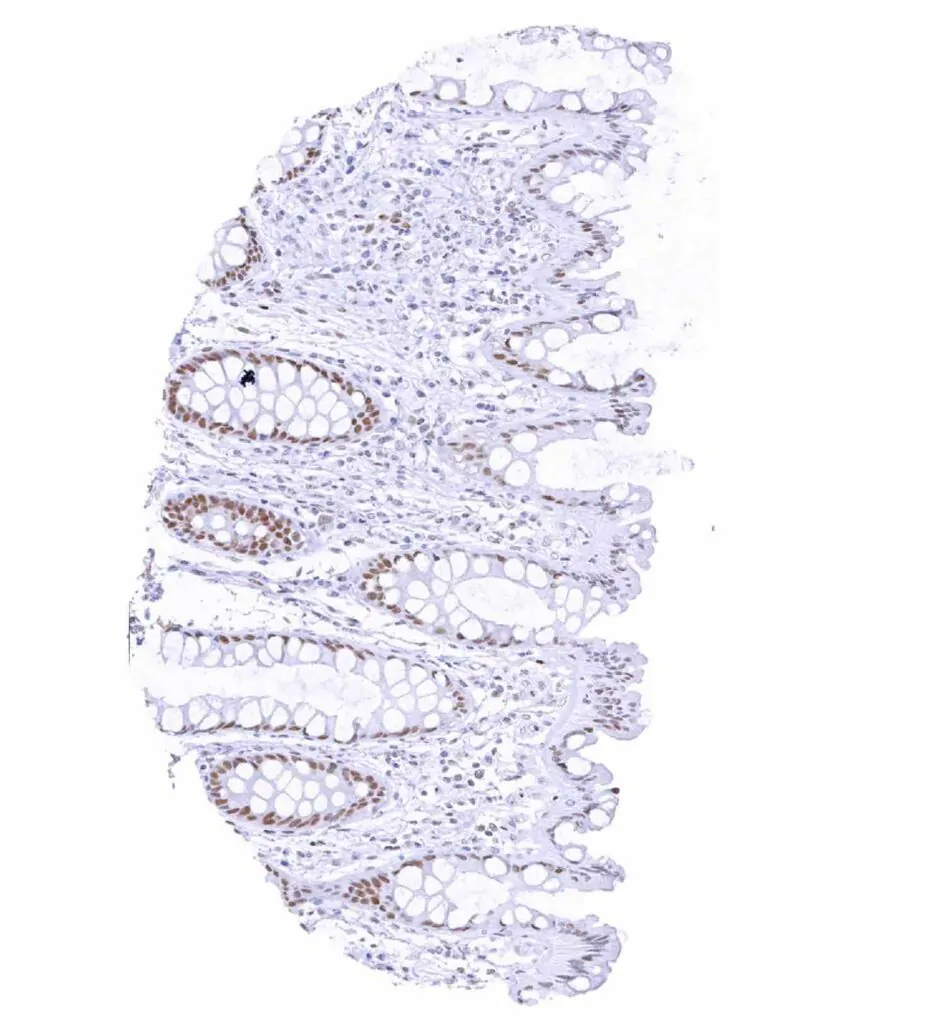

Colon descendens, mucosa – Weak to moderate TLE1 staining in epithelial cells. Staining is stronger in crypts than at the surface